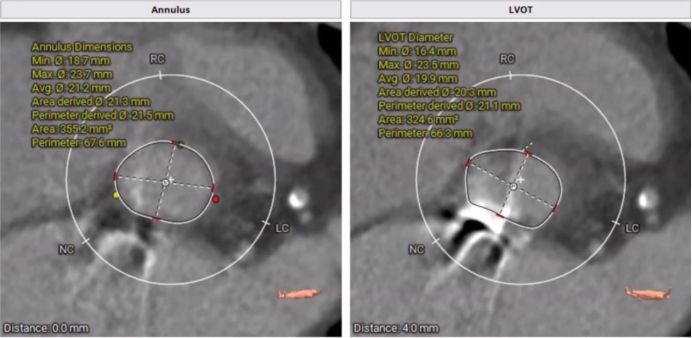

主动脉瓣膜CT影像

主动脉瓣增厚,回声增强,瓣叶钙化,开放轻度受限,关闭不拢,主动脉瓣环内径21mm;